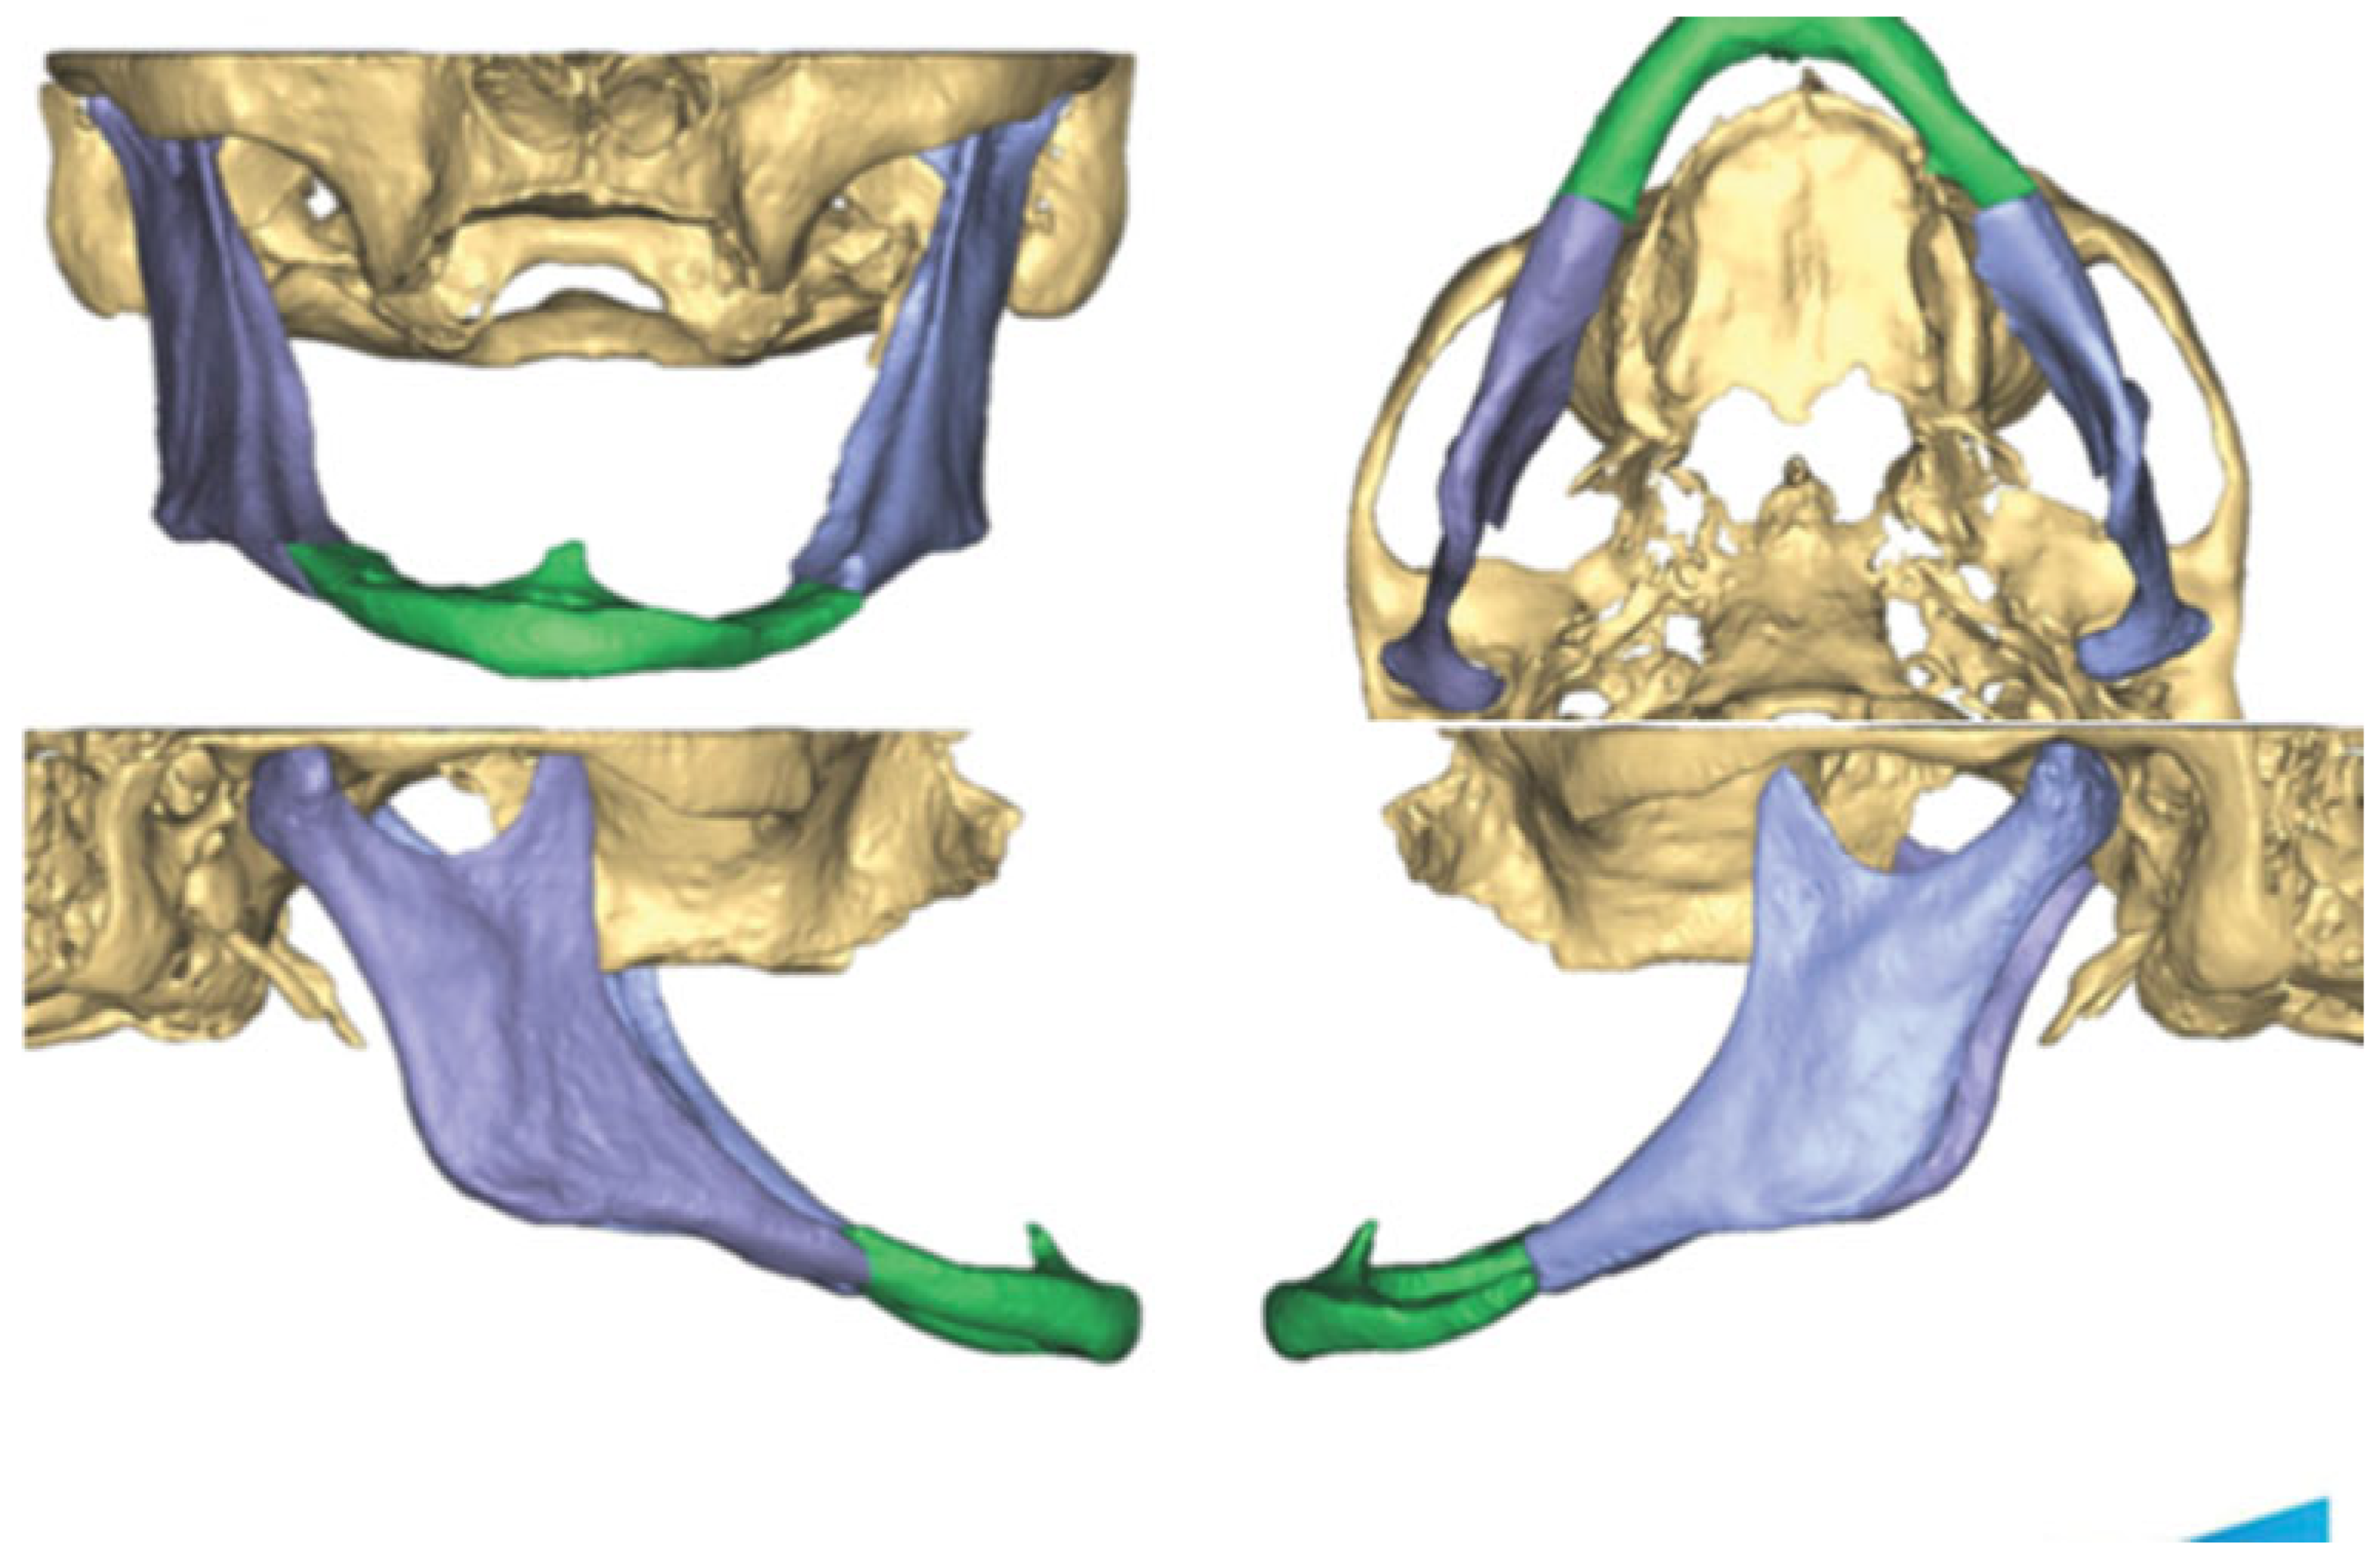

A 69-year-old woman had a fall 1 week prior to presentation while walking with her dog. She experienced worsening face and jaw pain and eventually presented to her primary medical doctor who ordered plain films and diagnosed her with a mandible fracture. She then self-referred herself to the authors for evaluation. Her past medical history was significant for chronic obstructive pulmonary disorder, hypothyroidism, hypercholesterolemia, anxiety, and depression. She stated that she recently quit smoking. Her dental history was significant for extraction of all upper and all lower teeth when she was in her 20s. On examination, she had moderate bruising of her neck bilaterally and submental area. Her intraoral mucosa was intact. A cone beam computed tomography (CBCT) was performed which showed bilateral mandibular body fractures as well as severe atrophy of the mandible, with the height of the mandible less than 4 mm at the fracture sites (Figure 1). Utilizing the DICOM data from the CBCT VSP was used utilizing Depuy Synthes/Materialise PROPLAN CMF. A 3-d image of the fractured mandible was constructed and the fracture was virtually reduced (Figure 2 and Figure 3). Stereolithographic models of the fractured and reduced mandible were fabricated and a bending template was adapted over the reduced mandible model and a 2.5 reconstruction plate was subsequently bent according to the template/model (Figure 4).

Figure 2. PROPLAN workup showing 3-d reconstruction of fractured mandible.

Figure 3. PROPLAN workup showing reduced mandible fractures.

Figure 4. Bending template adapted over stereolithographic model of reduced mandible.